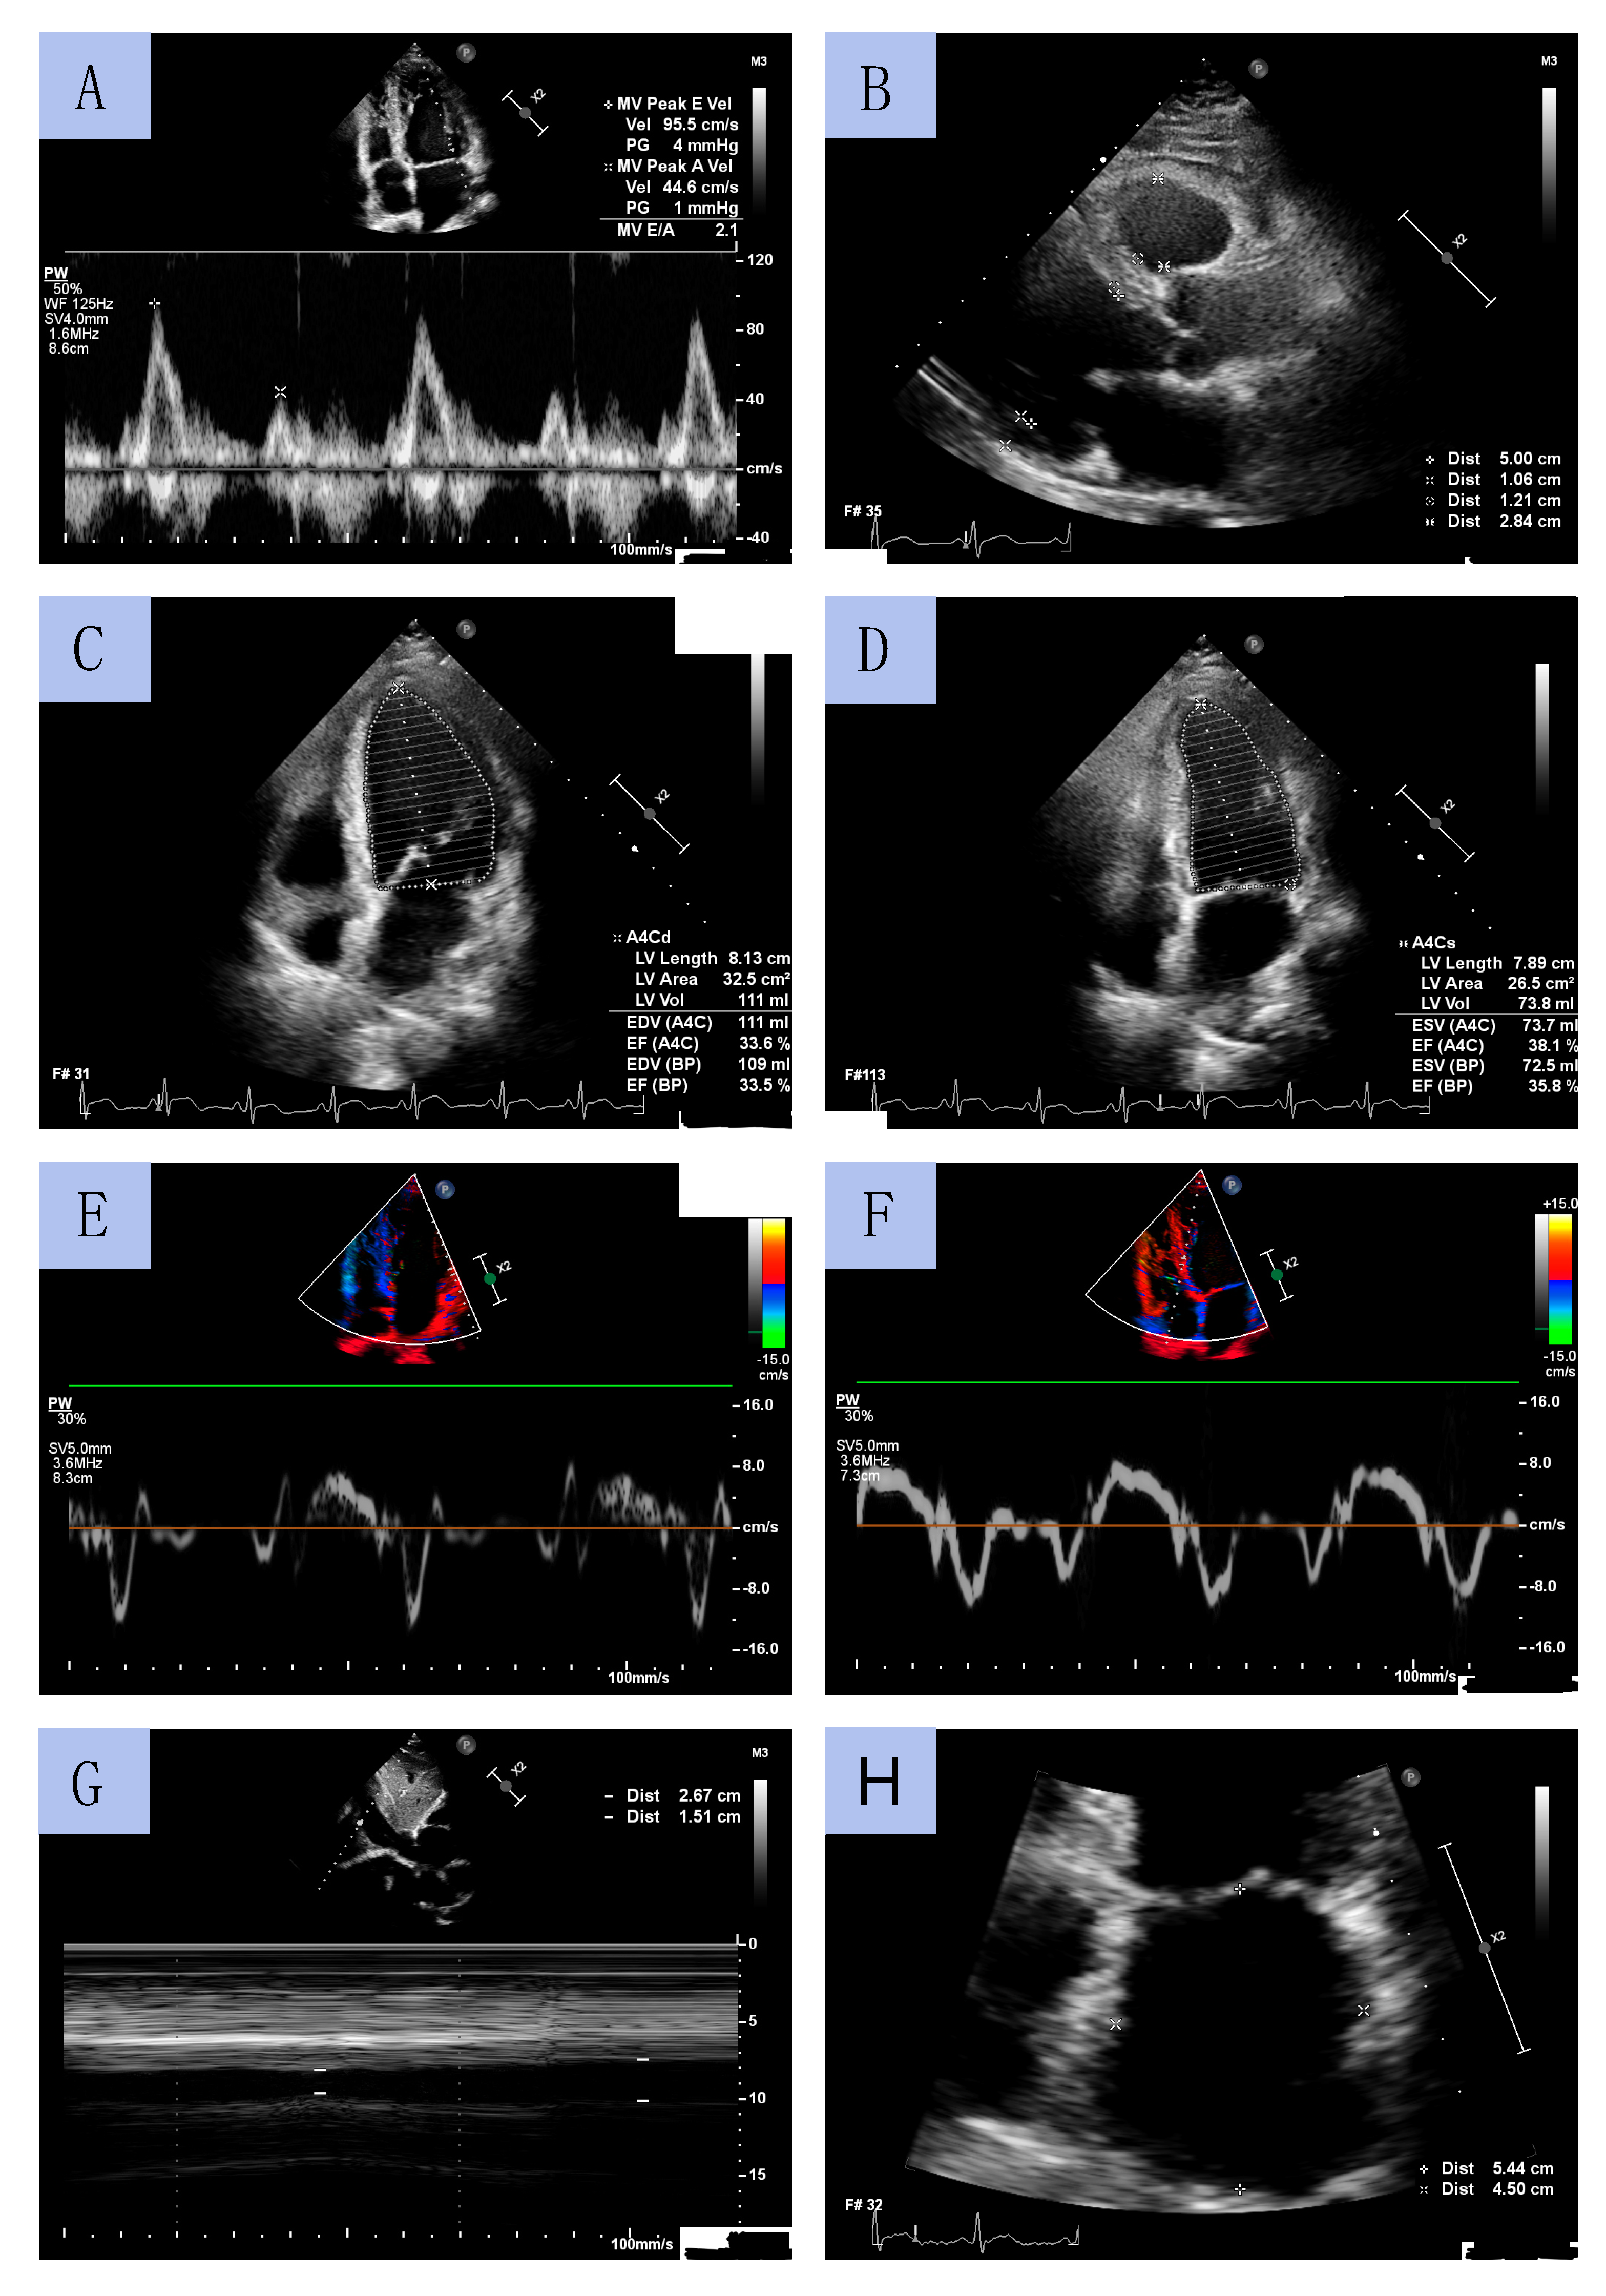

TTE was performed by experienced cardiac sonographers using a Philips Affinity 70 Ultrasound machine. All procedures were conducted in accordance with European Society of Cardiology (ESC) guidelines. LV diameters and wall thickness were measured using a parasternal long-axis view. LVEF was determined using Simpson’s method by measuring LV volume in systole and diastole obtained from apical four- and two-chamber views. LV mass index (LVMI) was calculated using the formula for estimation of LV mass from LV linear dimensions and indexed to body surface area (BSA). LV geometry was classified based on relative wall thickness (RWT). LA volume was assessed using the biplane area–length method from apical 2- and 4-chamber views at end-diastole from the frame preceding mitral valve opening and was indexed to BSA (LA volume index, LAVI). The early diastolic peak flow velocity (E velocity) and late diastolic peak flow velocity (A velocity) were assessed through pulsed wave Doppler from the apical 4-chamber view by positioning the sample volume at the tip of the mitral leaflets. Peak early diastolic tissue velocity (e’) and peak systolic tissue velocity (s’) were measured from the septal and lateral aspects of the mitral annulus. The E/e’ ratio was calculated as E velocity divided by mean e’ velocity (average value of the lateral and the septal velocity). The inferior vena cava (IVC) diameter was measured using M-mode echocardiography in subcostal view at end-expiration (IVCmax) and at inspiration (IVCmin). The IVC collapsibility (IVCC) was calculated as (IVCmax − IVCmin)/IVCmax and was expressed as a ratio. Sample echocardiographic measurements from selected patients are presented in Figure 3.

Figure 3.

Sample echocardiographic measurements: mitral diastolic peak flow velocities by pulsed wave Doppler (A); left ventricle diameters in long axis parasternal view (B); left ventricle geometry on end-diastole and end-systole (C,D); Tissue Doppler Imaging of tissue velocities of the lateral and septal aspects of the mitral annulus (E,F); the inferior vena cava collapsibility (G); left atrium diameters (H).